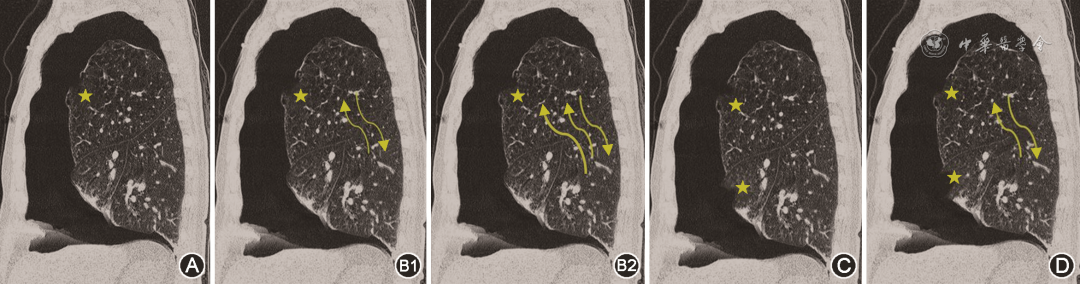

根据胸膜瘘口发生于一个肺叶或多个肺叶、不同肺叶之间是否存在侧支通气,可将气胸分为以下4种类型(图7)。(1)单纯型(A型):只有一个胸膜瘘口,且不存在侧支通气。(2)侧支通气型(B型):只有一个胸膜瘘口,但与其他肺叶之间存在侧支通气。侧支通气量较少为B1型,侧支通气量较大为B2型。(3)多发瘘口型(C型):在不同肺叶同时存在2个或2个以上瘘口。(4)多发瘘口伴侧支通气型(D型):存在多个胸膜瘘口,同时伴有侧支通气。

dcfd1b13bff681ad6fd078a8b7a9ab8d.png

图7难治性气胸的胸膜瘘口分型示意图。图A为单一瘘口,不伴侧支通气;图B1为单一瘘口伴少量侧支通气;图B2为单一瘘口伴大量侧支通气;图C为多叶段瘘口不伴侧支通气;图D为多叶段瘘口伴侧支通气